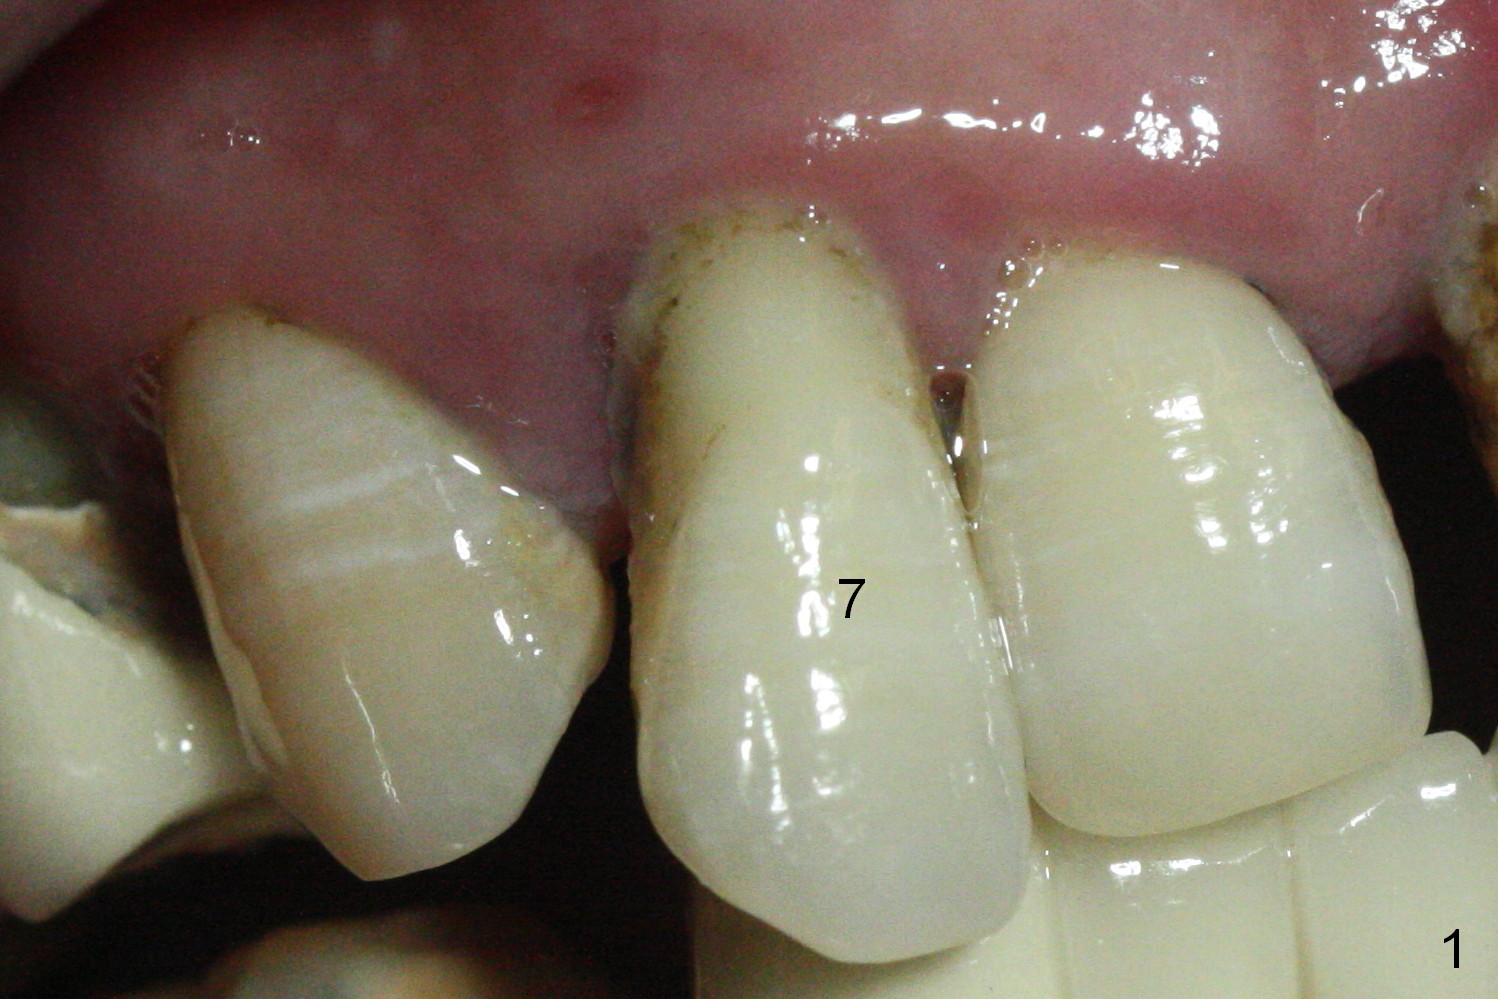

In fact the buccal plate feels to be perforated when 2 mm initial drill is being used probably at the deepest area of the concavity shown in Fig.2 (near B).  The trajectory is adjusted and the osteotomy is enlarged by 3 mm drill for 13 mm (Fig.3).  When a 3.8x13 mm implant is placed (50 Ncm), an angled abutment is used (Fig.4, 4.5x15°(A)5 mm).  As planned, a 3.8x13 mm implant is placed at #13, while bone graft is placed mesial and palatal to #15 implant.  No provisional is fabricated from #9 to 15 due to time limitation and lack of parallism between the abutments.